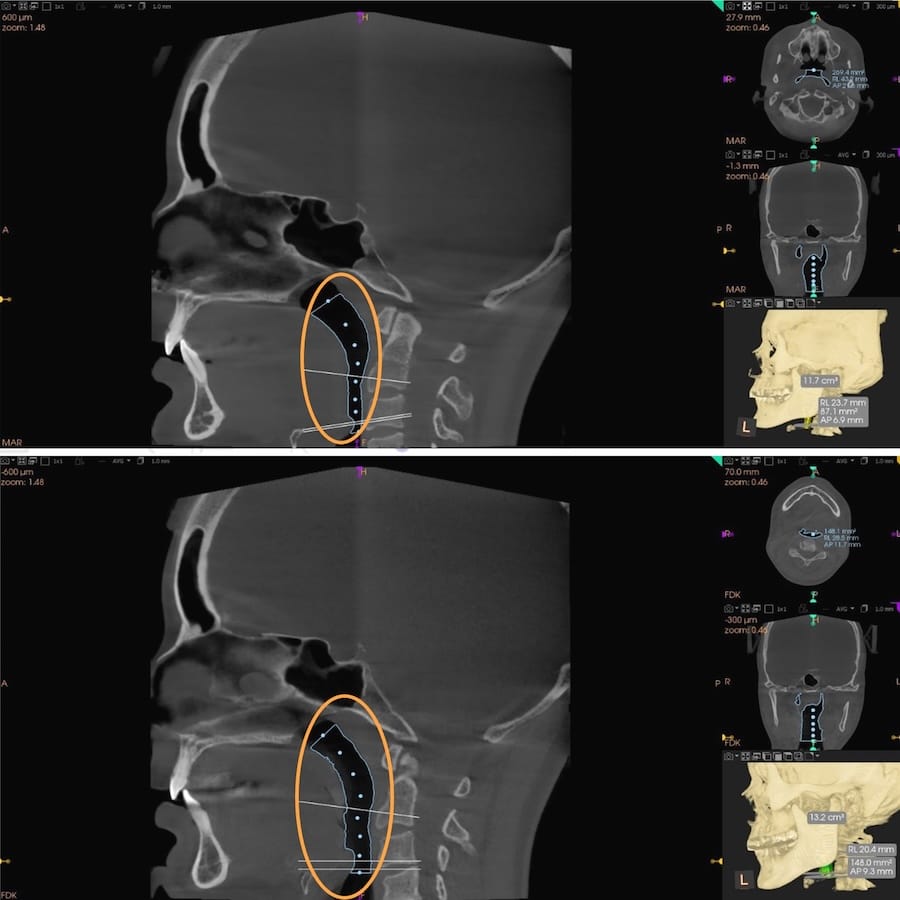

This same physiological response of changing the Disclusion Time from long to short can widen the airway constriction of a sleep apnea patient who wears a nighttime sleep appliance that forces his jaws apart, attempting to open his airway (Figures 13 and 14).11

Figure 13 – A CBCT comparison of airway volumes pre (top pane) to post Disclusion Time Reduction (bottom pane). A much wider airway followed the DTR-induced pharyngeal muscle relaxation (pre DTR Volume = 100.5 mm2; post DTR volume = 157.1 mm2). Note the post DTR airway is more parallel walled without being conically constricted pre-treatment.

Figure 14 – The airway constrictions compared pre (top pane) to post DTR (bottom pane) illustrate the patient’s airway widened following DTR. By gaining 57 mm2 of airway volume, this patient no longer needed his sleep appliance, slept more soundly, and experienced less apneic episodes.